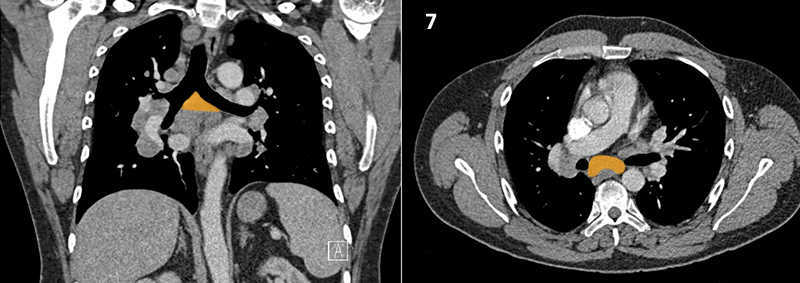

Nodal zones and stations according to the International Association for the Study of Lung Cancer (IASLC) node map.

Table (above): Nodal zones and stations according to the International Association for the Study of Lung Cancer (IASLC) node map. (Source: 1,2) *Depends on the side of the tumour.